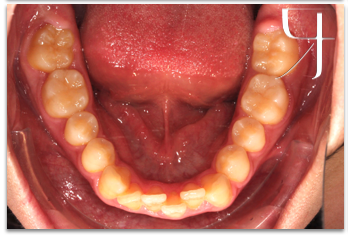

病患覺得自己的牙齒排列不整齊、擁擠,在吃東西以及清潔的時候無法清潔乾淨,而造成困擾,在高一的時候來找陳醫師矯正,後來病患在與媽媽討論之後,為了避免傳統矯正帶來的不適感以及不方便清潔而造成蛀牙,故選擇方便清潔、比較舒適的隱適美隱形牙套矯正;讓隱適美成為病患生活的一部分。

一般高中生年齡來找陳醫師做矯正的患者為數眾多,醫師會配合臉部外型、頭骨發育等基本面向先做評估,其次針對牙齒排列與臉部的相對位置等問題進一步評估。藉由隱形矯正的方式,將牙齒排列整齊;由於隱適美可以一至兩個月回診一次,也能節省在課業壓力較大時的回診時間。現在病患能夠很大方的開懷大笑、給予我們充滿自信的笑容!